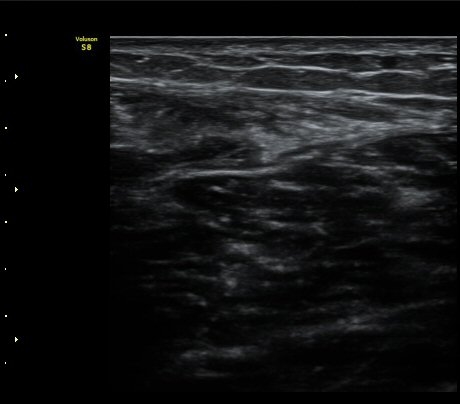

ÃÊÀ½ÆÄ °Ë»ç

¼ö»ó ÈÄ 2ÀÏ Â°

³»Ãø ºñº¹±Ù Á¾´Ü¸é°Ë»ç¿¡¼­ ±ÙÀ°°ú ÈûÁÙ ÀÌÇà ºÎÀ§¿¡ ÀÛÀº ÆÄ¿­°ú ¼ö¾× Àú·ù, ÆÄ¿­ µÈ

±ÙÀ°ÀÇ ±ÙÀ§ºÎ·Î ´ç°ÜÁüÀÌ °üÂû µÊ(±×¸² 1, 2, 3).